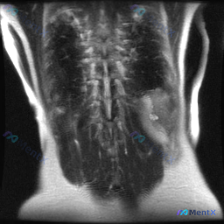

整理到一份有意思的影像读片资料: 本来是做腰椎及肾脏的MRI-T2冠状位,主要想看肾脏情况——结果肾脏看起来倒没明显占位、积水或结石,皮髓质分界也清;但腰椎这边,第一眼扫过去椎体排列好像有点不对劲? 原报告提了椎间盘信号略减低(考虑退变),但说“整体对称性良好”;后来重新看,有人明确指出冠状位上腰椎...

网上看到一份影像资料,申请原因写的是排查“Scoliosis(脊柱侧弯)”,拍的是腰椎MRI T2加权冠状位。 先不说侧弯,影像里有几个点先放出来: 1. 脊柱序列其实挺规整,椎间隙也对称,没看到明确的侧向成角畸形 2. 但两侧腰大肌区域里有明显的圆形/类圆形高信号囊性灶 3. 右侧病灶还和肾脏结构...

整理到一份腰椎MRI的影像分析资料,第一眼看到的是很明确的脊柱问题: - 腰椎向右侧凸,凹侧在左 - 多节段椎间盘T2信号减低,凹侧椎间隙更窄 - 椎体边缘有骨赘形成 但再往下看,影像里还提到了一个脊柱外的意外发现,而且风险等级可能比脊柱侧凸更高… 想先问问大家:如果是你拿到这份只有冠状位的腰椎MR...